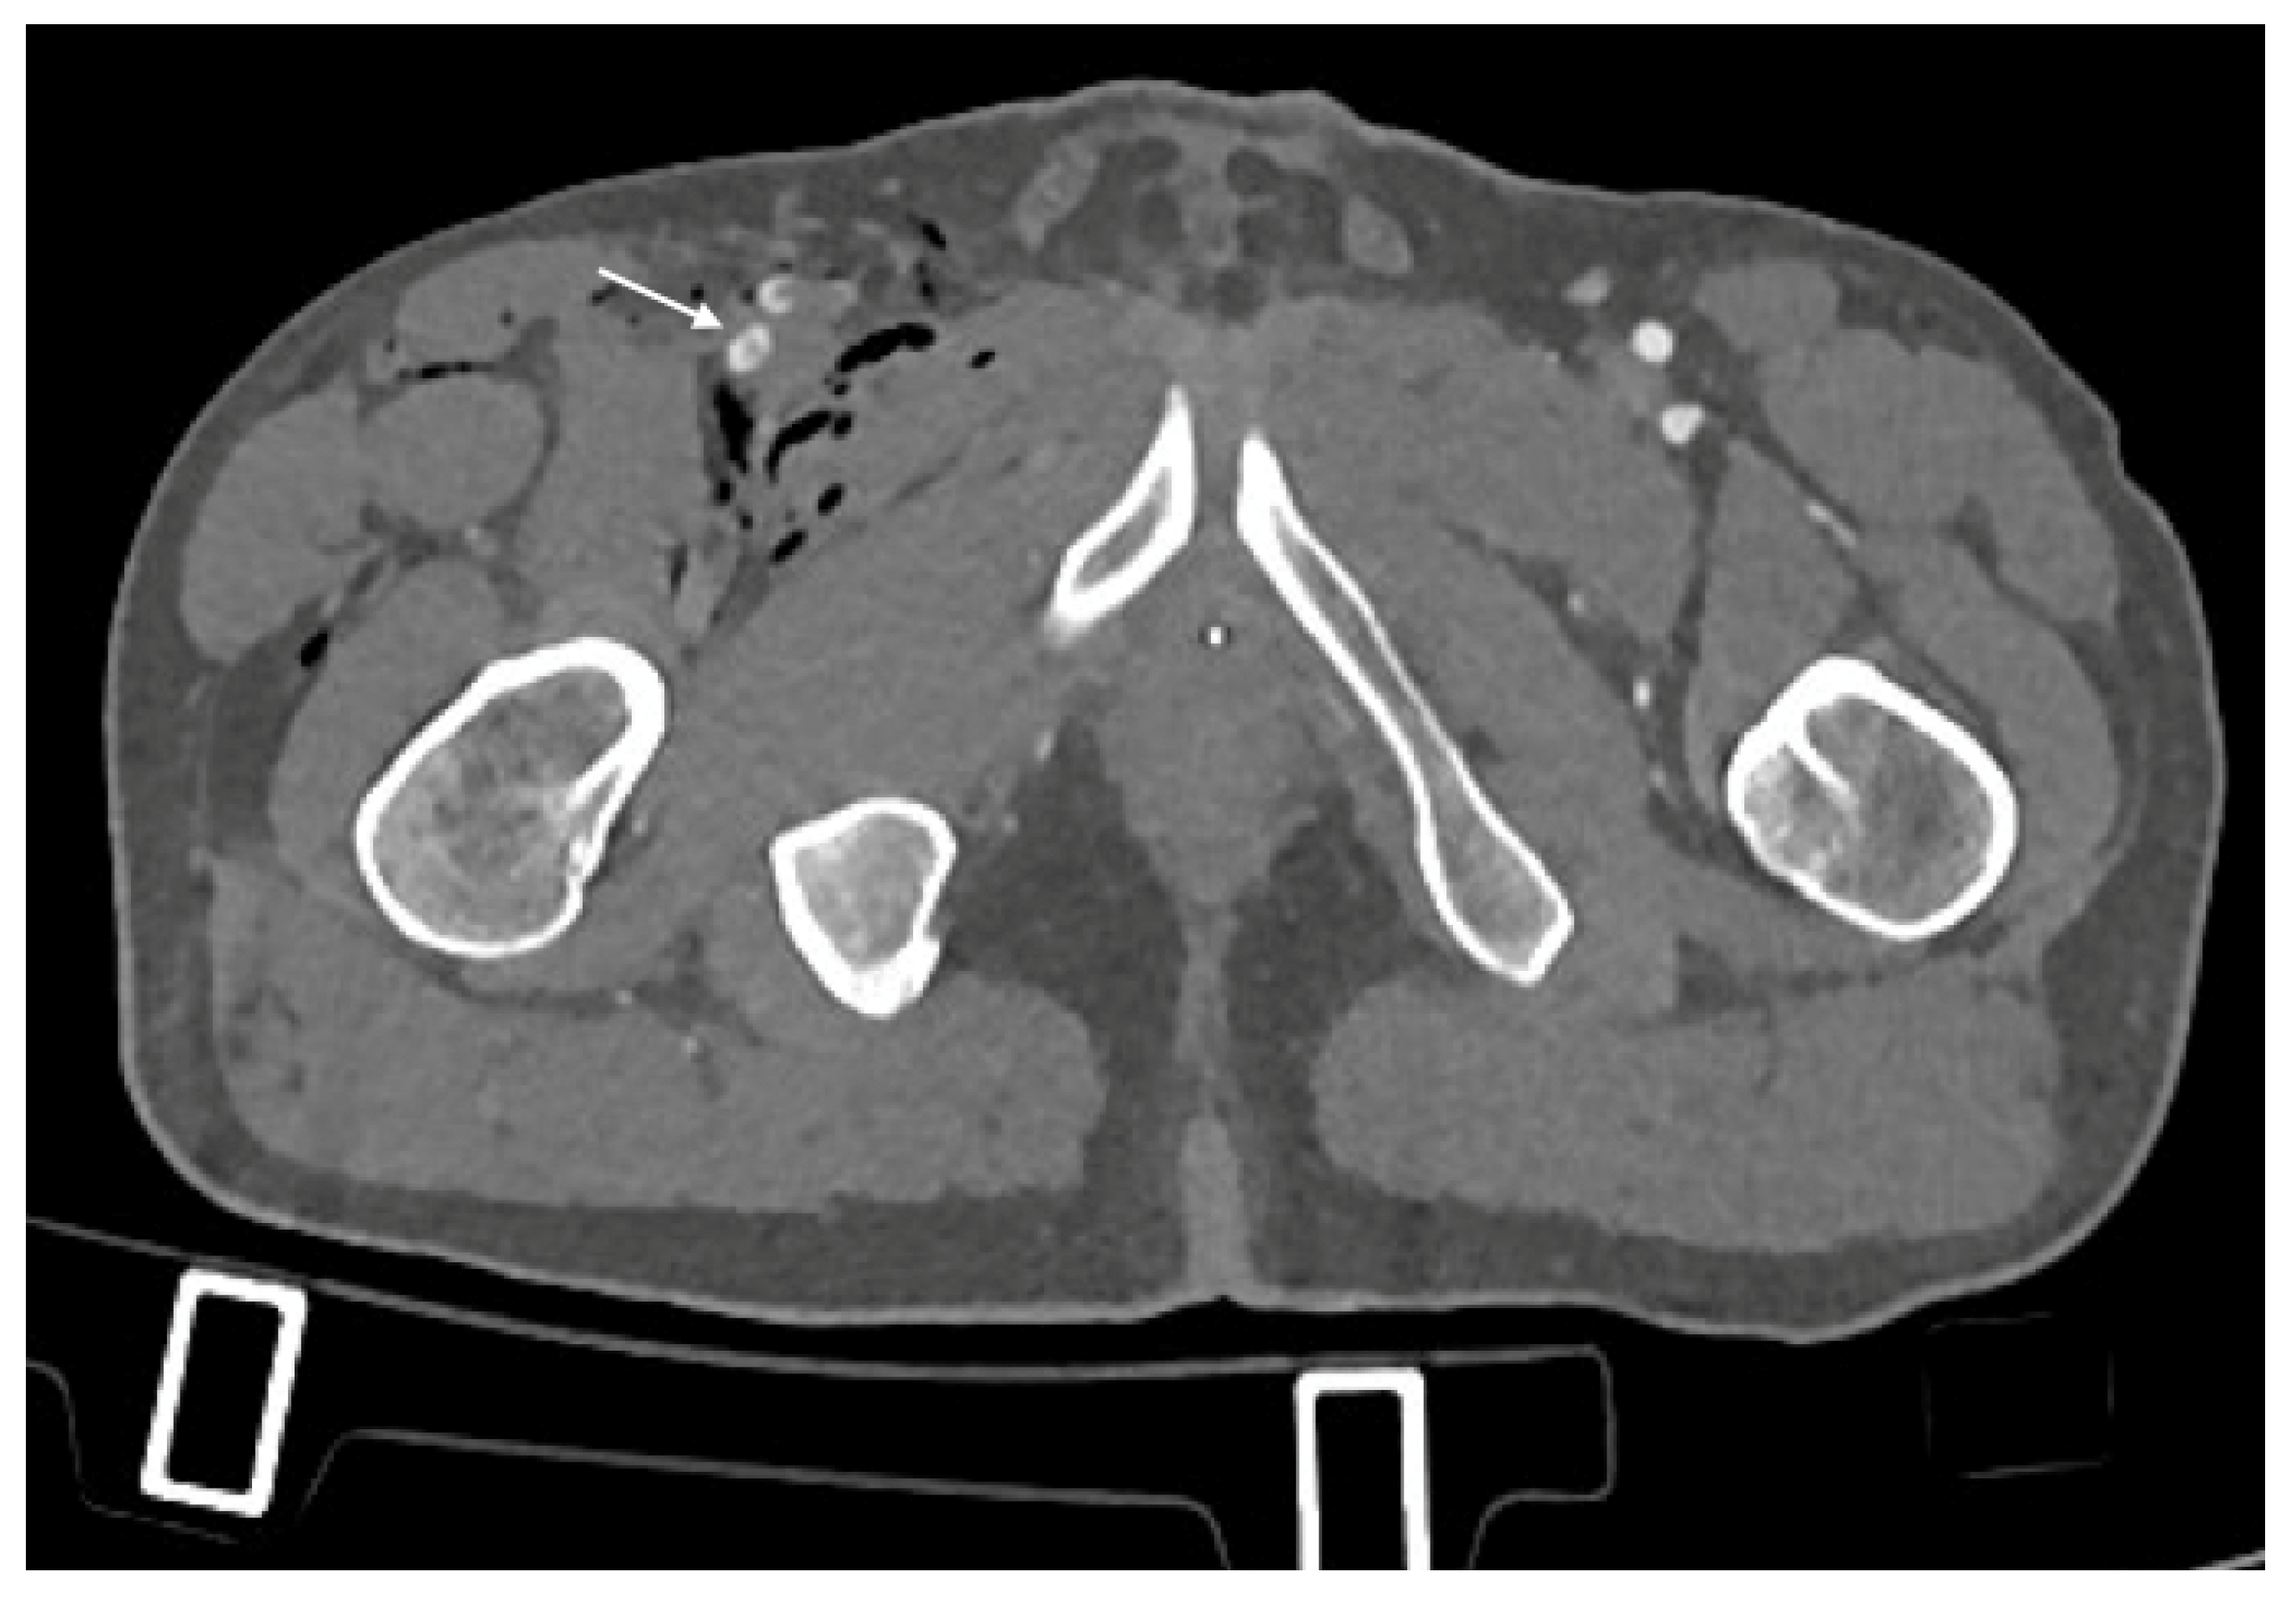

- Pseudoaneurysm is caused by focal arterial wall tear involving intimal and medial layers, and represents a collection of blood contained only by the adventitia layer or surrounding tissue [5,56,59]. It appears as an outpouching sac with a round and smooth margin in continuity with the arterial adjacent lumen (Figure 4). Pseudoaneurysm bleeding appears as irregular, lobulated perilesional contrast blush [65,68]. Pre-exiting calcification or pseudoaneurysm should be differentiate form active bleeding; delayed phase acquisition can be useful because in active bleeding the contrast extravasation dissipates along tissue planes instead pseudoaneurysm and calcification remain stable [60,67].